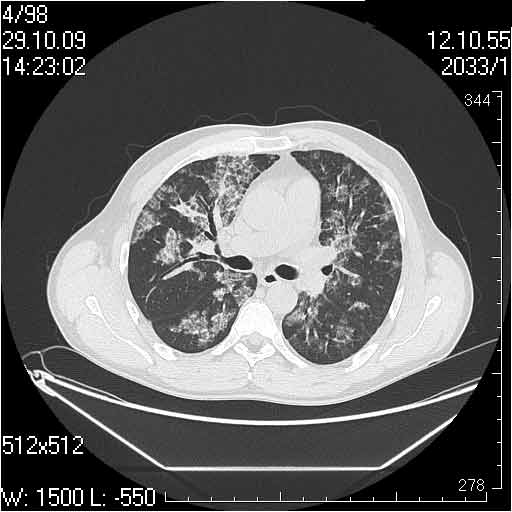

Случай №2

Мужчина 54 лет

Случай 2: картина патологических изменения довольно типична: GGOs & thickened interlobular septas = "crazy paving" sign. Наличие плотностей по типу матового стекла в сочетании с утолщением междолевых перегородок, даёт признак булыжной мостовой; на первом месте будет стоят диагноз альвеолярных протеиноз.